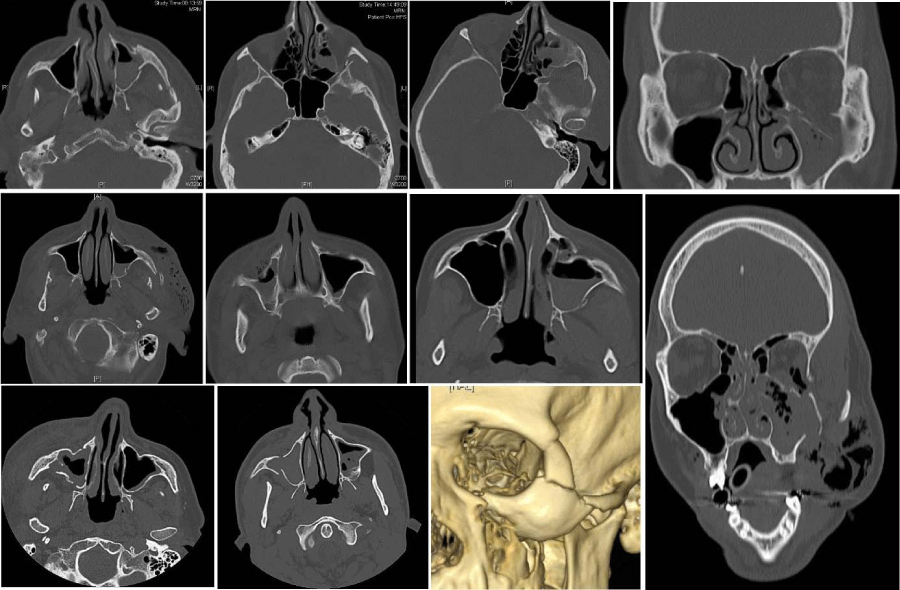

Figure 2:

Samples of study-CAT-scans of patients aged 70+ showing minimal/below critical-size-defect dislocations of isolated zygoma-tripod and/or arch-fractures and related fractures of the orbital-floor.

Figure 3:

Samples of study-CAT-scans of patients aged 70+ showing above critical-size-defect dislocations of isolated zygoma-tripod and/or arch-fractures and related fractures of the orbital-floor.

a) Fractures with no or minimal dislocation (max. 1 - 2,7 mm) and no fracture-stages/fracture-crepitations/maxillary mobility palpable in clinical investigation (Figure 2)

b) Fractures with dislocations above critical-size-defects (2,7mm [17Udagawa A, Sato S, Hasuike A, Kishida M, Arai Y, et al. (2013) Micro CT observation of angiogenesis in bone regeneration. Clin Oral Implants Res 24: 787-792.]) and/or fracture-stages/fracture-crepitations/maxillary mobility palpable in clinical investigation (Figure 3)